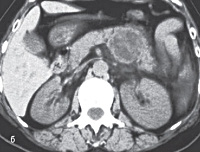

• КТ поджелудочной железы. С помощью томографии определяют точные размеры эхинококкового пузыря, его расположение по отношению к смежным анатомическим структурам. В ходе исследования визуализируется плотная кальцинированная оболочка и мембраны дочерних пузырьков.